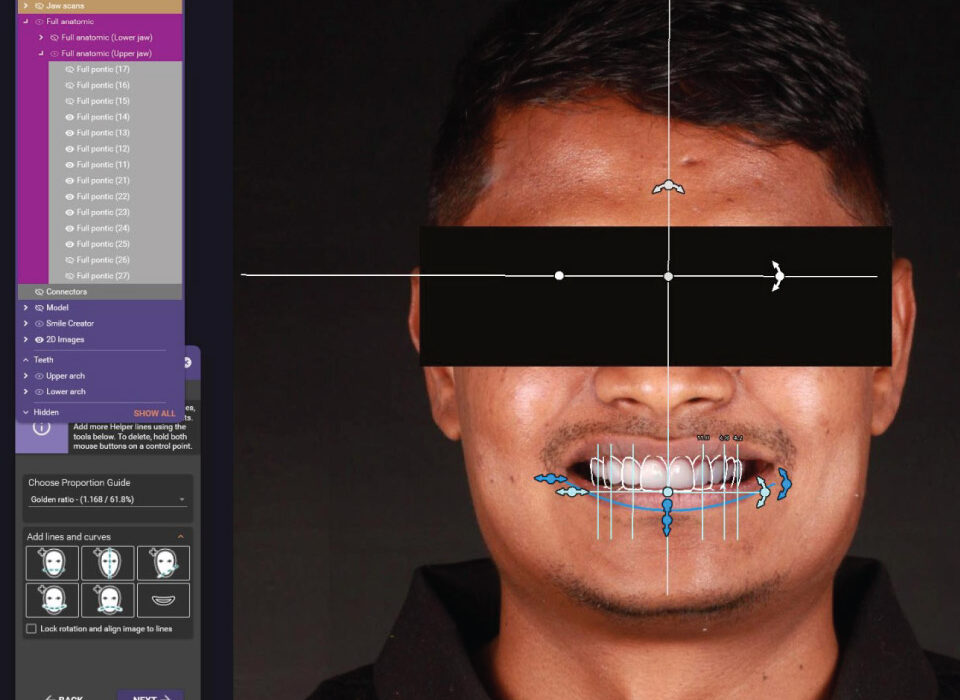

Smile Designing

Highly Advanced & Biocompatible Lithium Di Silicate glass ceramic ingots for life like restorations for enhanced translucency – synergizing aesthetics and function.